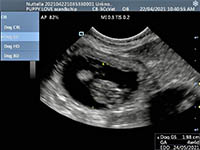

Mobile Ultrasound Pregnancy Scanning and Microchipping Services

Puppy Love scan and chip